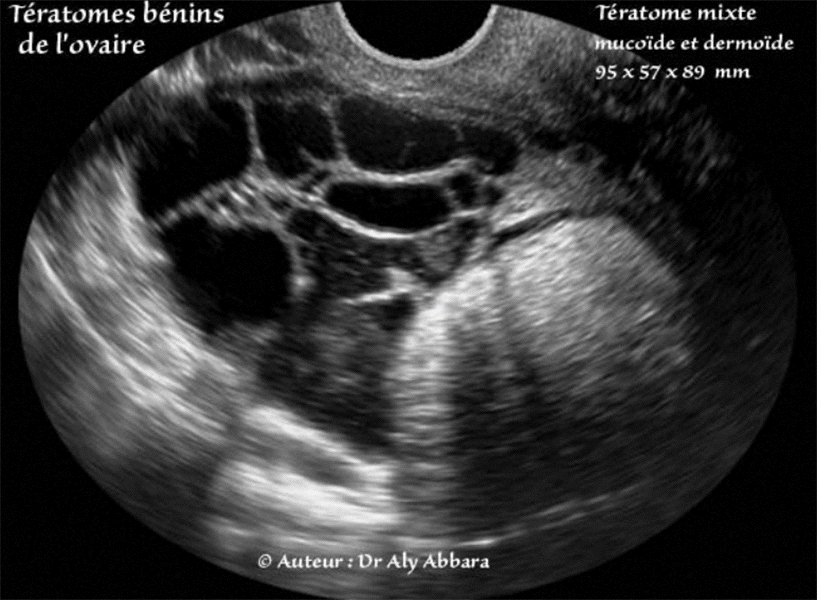

Tératome bénin de l'ovaire (kyste dermoïde) comportant une composante mucineuse (kyste mucineux bénin)

5 % des tératomes bénins de l'ovaire comportent une composante mucineux (cystadénome mucineux)

Série d'images échographiques montrant les différents aspects et la composition d'une tumeur ovarienne comportant deux composante : dermoïde et mucineuse.

L'examen anato-pathologique du premier tératome bénin multissulaire présenté dans cette série est le suivant :

Tumeur kystique à surface est bosselée, mais sans végétation externe. La cavité principale contient un matériel jaunâtre pâteux constitué par du sébum et des cheveux. Plusieurs cavités accessoires renferment un contenu filant et translucide. Un fragment d'os et une dent sont visibles dans la paroi kystique.

Histologiquement, la cavité principale est tapissée par une bordure de type épidermique souvent détruite par réaction gigatocellulaire. Des annexes sudoripares et sébacées nombreuses sont visibles dans la paroi. D'autres cavité sont tapissées par bordure cylindrique mucipare parfaitement régulière reposant sur une bande de tissu conjonctif renfermant quelques adipocytes, quelques trousseaux musculaires lisses et occasionnellement quelques petites bandes de tissu glial.

Conclusion : dysembryome pluritissulaire complexe, mature (kyste dermoïde) de l'ovaire droit. Pas de signe histologique de malignité.